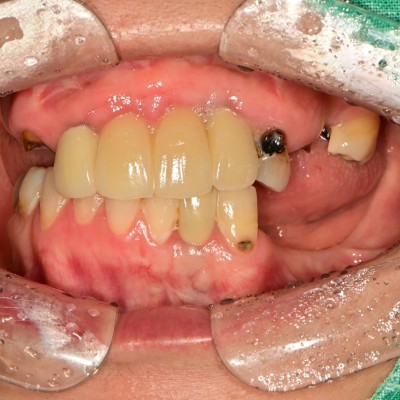

만 50세 전체 임플란트 증례입니다. 전체 임플란트 증례입니다. 18개의 임플란트로 완성하였습니다.

47세 전체임플란트 증례 전체임플란트로 진행하였습니다.